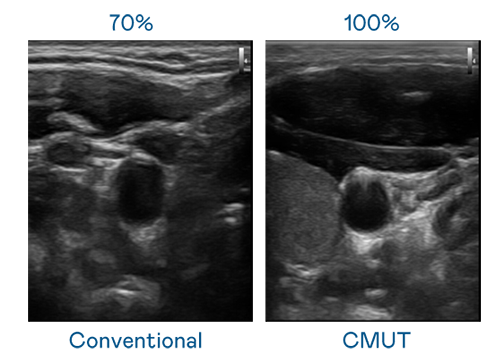

CMUT 技術是一種用電容式微機電元件來產生超音波訊號的技術。與傳統 PZT 壓電式技術相比,CMUT 頻寬增加 30%,更寬頻的超音波訊號讓影像解析度大幅提升,是實現高影像品質醫療超音波掃描、促進精準醫療發展的關鍵技術。

超音波影像的解析度高低,首先取決於探頭能發出的訊號頻寬。stake CMUT 可提供高清晰的超音波訊號,提供高頻寬、高靈敏度、影像紋理細節更高的超音波影像,協助醫護人員縮短影像判讀時間及利用精準的醫療影像進行診斷。